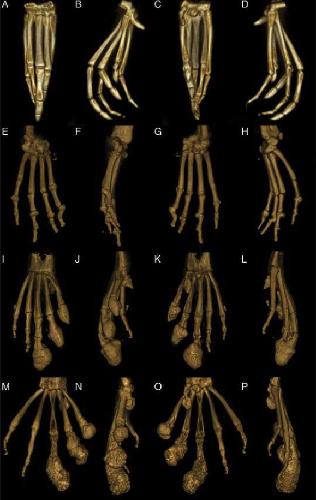

Degenerative Osteoarthropathy in Laboratory Housed Xenopus (Silurana) tropicalis., Zhang M, Wilson SS, Casey KM, Thomson PE, Zlatow AL, Langlois VS, Green SL., Comp Med. December 1, 2021; 71 (6): 512-520.

Axial Skeletal Malformations in Genetically Modified Xenopus laevis and Xenopus tropicalis., Zlatow AL, Wilson SS, Bouley DM, Tetens-Woodring J, Buchholz DR, Green SL., Comp Med. December 1, 2020; 70 (6): 532-541.